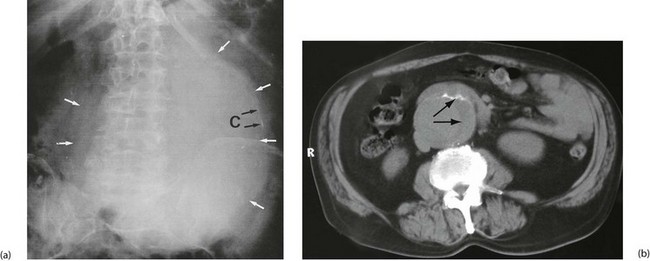

Aorto-iliac aneurysms are often found incidentally. The patient may notice a pulsatile abdominal mass or a pulsatile mass may be discovered on abdominal examination. An aneurysm may also be noticed incidentally on radiological investigation—as calcification on a plain abdominal X-ray, as an obvious aneurysm on CT or, most commonly, on ultrasound scanning for obstructive urinary symptoms (see Fig. 42.2). More recently in the UK, a national AAA screening programme has been approved, with the aim of offering all men an ultrasound scan of the abdominal aorta on reaching 65. Similar schemes are appearing in Denmark, Australia and other countries.

Degenerative aneurysms are usually fusiform, slowly expanding in diameter. As it enlarges, the vessel wall thins, expansion accelerates and the risk of rupture increases. Most abdominal aortic aneurysms involve only the infrarenal aorta; some extend distally to involve common iliac arteries; sometimes there are separate aneurysms of internal iliac arteries (see Fig. 42.1). A few extend proximally to become thoraco-abdominal aneurysms.